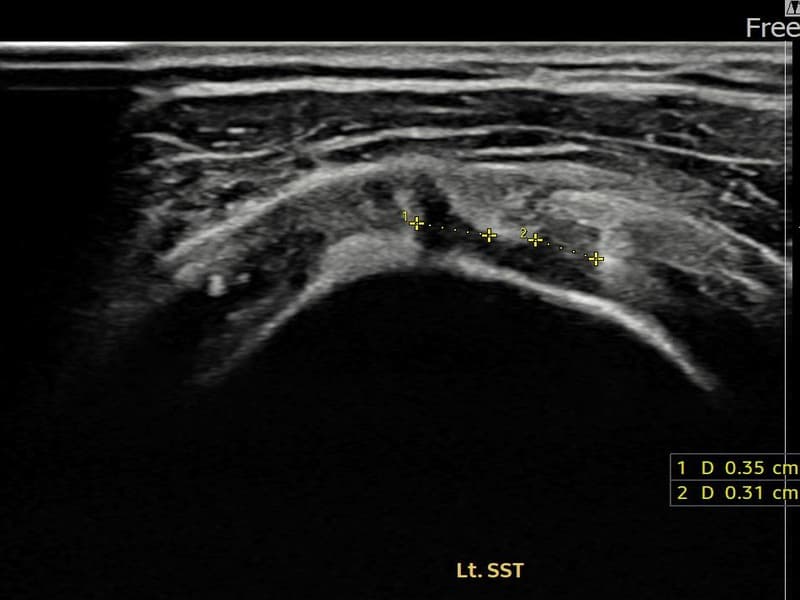

超音波検査にて左 棘上筋腱 関節面側部分断裂(3.5mm × 3.1mm (부분파열))を確認。縫縮術施行後、腱の連続性が回復し、日常生活に復帰されました。

施術前

術前超音波にて左 棘上筋腱 関節面側部分断裂・左肩棘上筋腱のエコー不連続と腱欠損(3.5mm × 3.1mm (부분파열))を確認。術後超音波では断裂部位が再生組織で充填され、腱の連続性回復とエコーパターンの正常化が確認されました。

持続する左肩痛で来院された患者様です。超音波検査にて左 棘上筋腱 関節面側部分断裂(欠損:3.5mm × 3.1mm (부분파열))を確認し、超音波ガイド下で非手術的縫縮術を施行しました。術後は約4〜6週間のブレース装着の後、段階的なリハビリプログラムを実施。経過超音波で腱の連続性回復を確認し、患者様は無事に日常生活へ復帰されました。